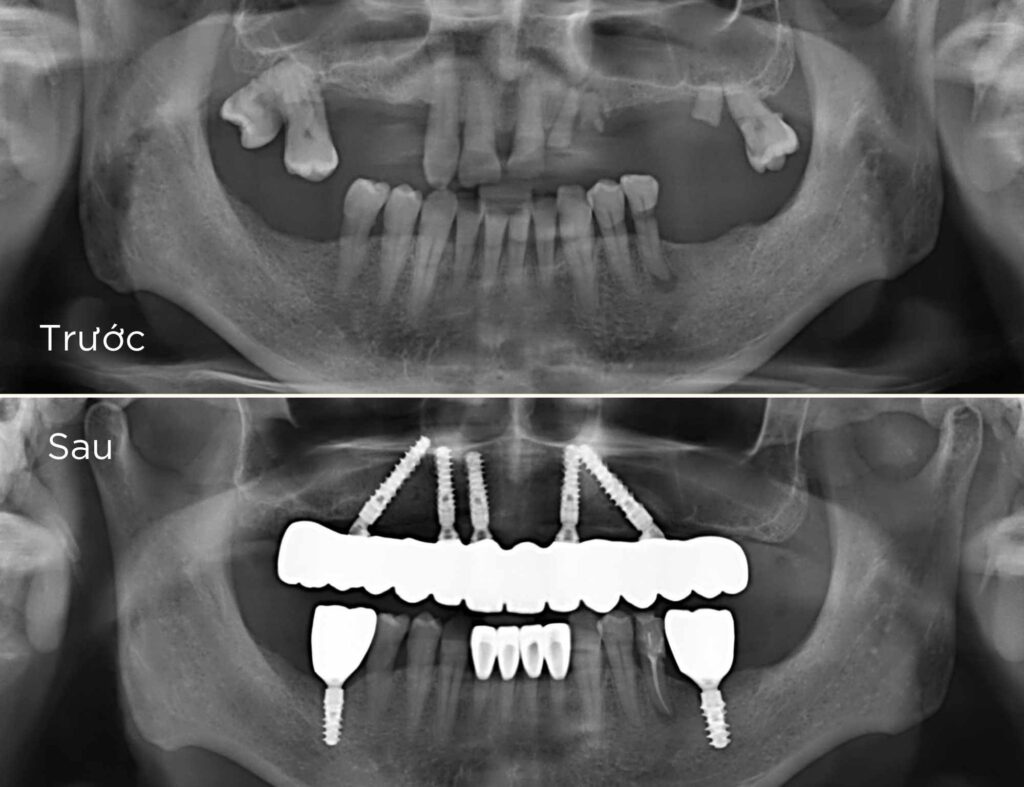

- 1. Khám và tư vấn: Bác sĩ sẽ khám và tư vấn chi tiết về tình trạng răng miệng của bạn, đánh giá liệu bạn có phù hợp để cấy ghép implant hay không.Chụp X-quang và lập kế hoạch điều trị: Chụp X-quang để xác định cấu trúc xương hàm, từ đó lập kế hoạch cấy ghép chi tiết.

- 2. Chụp X-quang và lập kế hoạch điều trị: Chụp X-quang để xác định cấu trúc xương hàm, từ đó lập kế hoạch cấy ghép chi tiết.

- 4. Lên kế hoạch và thiết kế máng hướng dẫn cắm implant 3D: Tại nha khoa Ken bạn có thể an tâm là implant sẽ được đặt ở vị trí đúng theo 3 chiều không gian - để có thể chịu lực ăn nhai tối ưu như răng thật. Các trụ implant sẽ được đặt vào trong xương qua máng hướng dẫn phẫu thuật được thiết kế trong phần mềm kỹ thuật số đảm bảo an toàn và độ chính xác cao.

- 5. Phẫu thuật đặt implant: Đặt các trụ implant vào xương qua máng hướng dẫn phẫu thuật kỹ thuật số và được tiến hành bởi bác sĩ chuyên khoa.

- 6. Phục hình tạm trên implant toàn hàm ALL-ON-X: Trong các trường hợp bệnh nhân mất răng toàn hàm phục hình tạm được gắn cho bệnh nhân ngay sau khi phẫu thuật.

- 8. Phục hình sứ trên implant toàn hàm ALL-ON-X: Sau khi các trụ implant đã tích hợp trong xương hàm, phục hình tạm trước đó sẽ được thay thế bời phục hình sứ.